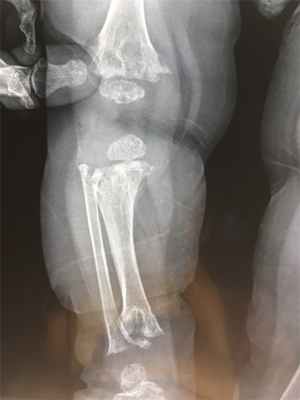

Лабораторные данные. Рентгенограммы. На рентгенограммах черепа обнаружены лобный и затылочный гиперостозы и/или склероз. Основание черепа обычно плотное с облитерированными параназальными синусами и с недостаточной пневматизацией сосцевидного отростка. Отмечается гипертелоризм. В течение первых 6 лет жизни метафизы длинных костей начинают приобретать булавовидную форму, выраженную значительно слабее, чем это наблюдается при болезни Пиле (метафизарной дисплазии), и могут быть на протяжении раннего детства минимальным и. У маленьких детей и в старшем возрасте встречается диафизарный склероз, но с возрастом он исчезает (Beckman, Walker). В коротких трубчатых костях обнаруживаются те же самые изменения, что и в длинных костях. Может быть расширена грудинная половина ключиц. Таз и латеральная часть позвоночника нормальные. В некоторых случаях отмечается сужение внутреннего слухового прохода (Rimoin et al.). Политомограммы показали, что область улитки заполнена костью (Gladney, Monteleone).

Краниометафизарная дисплазия - остеохондродисплазия, характеризующаяся гиперостозом и склерозом черепно-лицевых костей и расширением метафизов. Часто данное заболевание принимают за болезнь Пайла (множественную метафизарную дисплазию), однако при краниометафизарной дисплазии наблюдается более выраженный гиперостоз черепа и меньшее расширение метафизов. Для заболевания характерно утолщение свода и склероз основания черепа, утолщение костей лицевого черепа, макроцефалия, относительно короткий нос, отличительным признаком является толстый костный выступ над переносицей. У пациентов наблюдается гипертелоризм глаз, экзофтальм, сдавление черепных нервов, головная боль, узкие носовые ходы и заложенный нос. В конечностях отмечается легкое или умеренное расширение и склероз метафизов, наиболее заметные на дистальном конце бедренной кости, Х-образное искривление ног.

Это аутосомно-доминантное заболевание Аутосомно-доминантные Генетические нарушения, вызванные изменениями в одном гене («Менделевские нарушения»), являются самыми простыми для анализа и наиболее хорошо поняты. Если экспрессия признака требует только. Прочитайте дополнительные сведения человека обусловлено мутациями гена ANKH. В раннем детстве образуются параназальные бугры, а также прогрессирующее расширение и утолщение костей черепа и нижней челюсти, что приводит к деформации лица и челюсти. Поражение костей вовлекает черепные нервы, вызывая дисфункцию. Исправление прикуса зубов Неправильный прикус Неправильный прикус является ненормальным контактом между зубами верхней и нижней челюсти. (См. также Обследование пациентов со стоматологическими заболеваниями [Evaluation of the Dental Patient]. Прочитайте дополнительные сведенияДиагноз краниометафизарной дисплазии предполагается при наличии типичных черепно-лицевых аномалий, которые иногда сочетаются с повышенной восприимчивостью к респираторным инфекциям, или нарушение может быть обнаружено во время оценки дисфункции черепных нервов, которые могут возникнуть в результате защемления у основания черепа. Как правило, проводят обычное рентгенологическое исследование. Рентгенологические изменения являются возрастными и обычно проявляются в возрасте 5 лет. Склероз является главной особенностью черепа. В трубчатых костях отмечаются булавовидные расширения метафизов, особенно в области дистальной части бедренной кости. Однако, эти изменения являются менее серьезными, чем при болезни Пайла Метафизарная дисплазия (болезнь Пайла) Краниотубулярные дисплазии включают минимальный остеосклероз с нормальным формированием скелета. Остеопетроз является наследственным заболеванием, характеризуется повышенной плотностью костной. Прочитайте дополнительные сведения . Позвоночник и таз не поражены.

Диагноз метафизарной дисплазии обычно ставят при проведении рентгенографии по несвязанным причинам. Рентгенологические изменения являются патогномоничными. Длинные кости недостаточно деформированы, и наружный слой кости, как правило, тонкий. Трубчатые кости ног имеют грубое расширение книзу, подобно колбе Эрленмейера, особенно в дистальной части бедренной кости. Кости малого таза и грудной клетки расширены. Тем не менее, череп, в основном, не затронут.

Намного больше информации при краниометафизарной дисплазии дают рентгенологические методы исследования скелета. На рентгенограммах черепа при аутосомно-доминантной форме заболевания определяются уплотнение костной ткани в области затылочной кости, склероз основания черепа, пониженная пневматизация синусов и ячеек височной кости. В ряде случаев может выявляться склероз межкостных швов и расширение метафизов трубчатых костей. При аутосомно-рецессивном типе краниометафизарной дисплазии на рентгенограммах обнаруживаются схожие, но намного более выраженные нарушения, например – полное отсутствие околоносовых пазух, резкое сужение и иногда заполнение костной тканью отверстий черепно-мозговых нервов. Кроме того, наблюдается склероз не только основания, но и свода черепа, в ряде случаев определяются значительные деформации костей лицевого отдела. Немного сильнее, чем при доминантном типе, выражены расширение и склероз метафизов трубчатых костей.